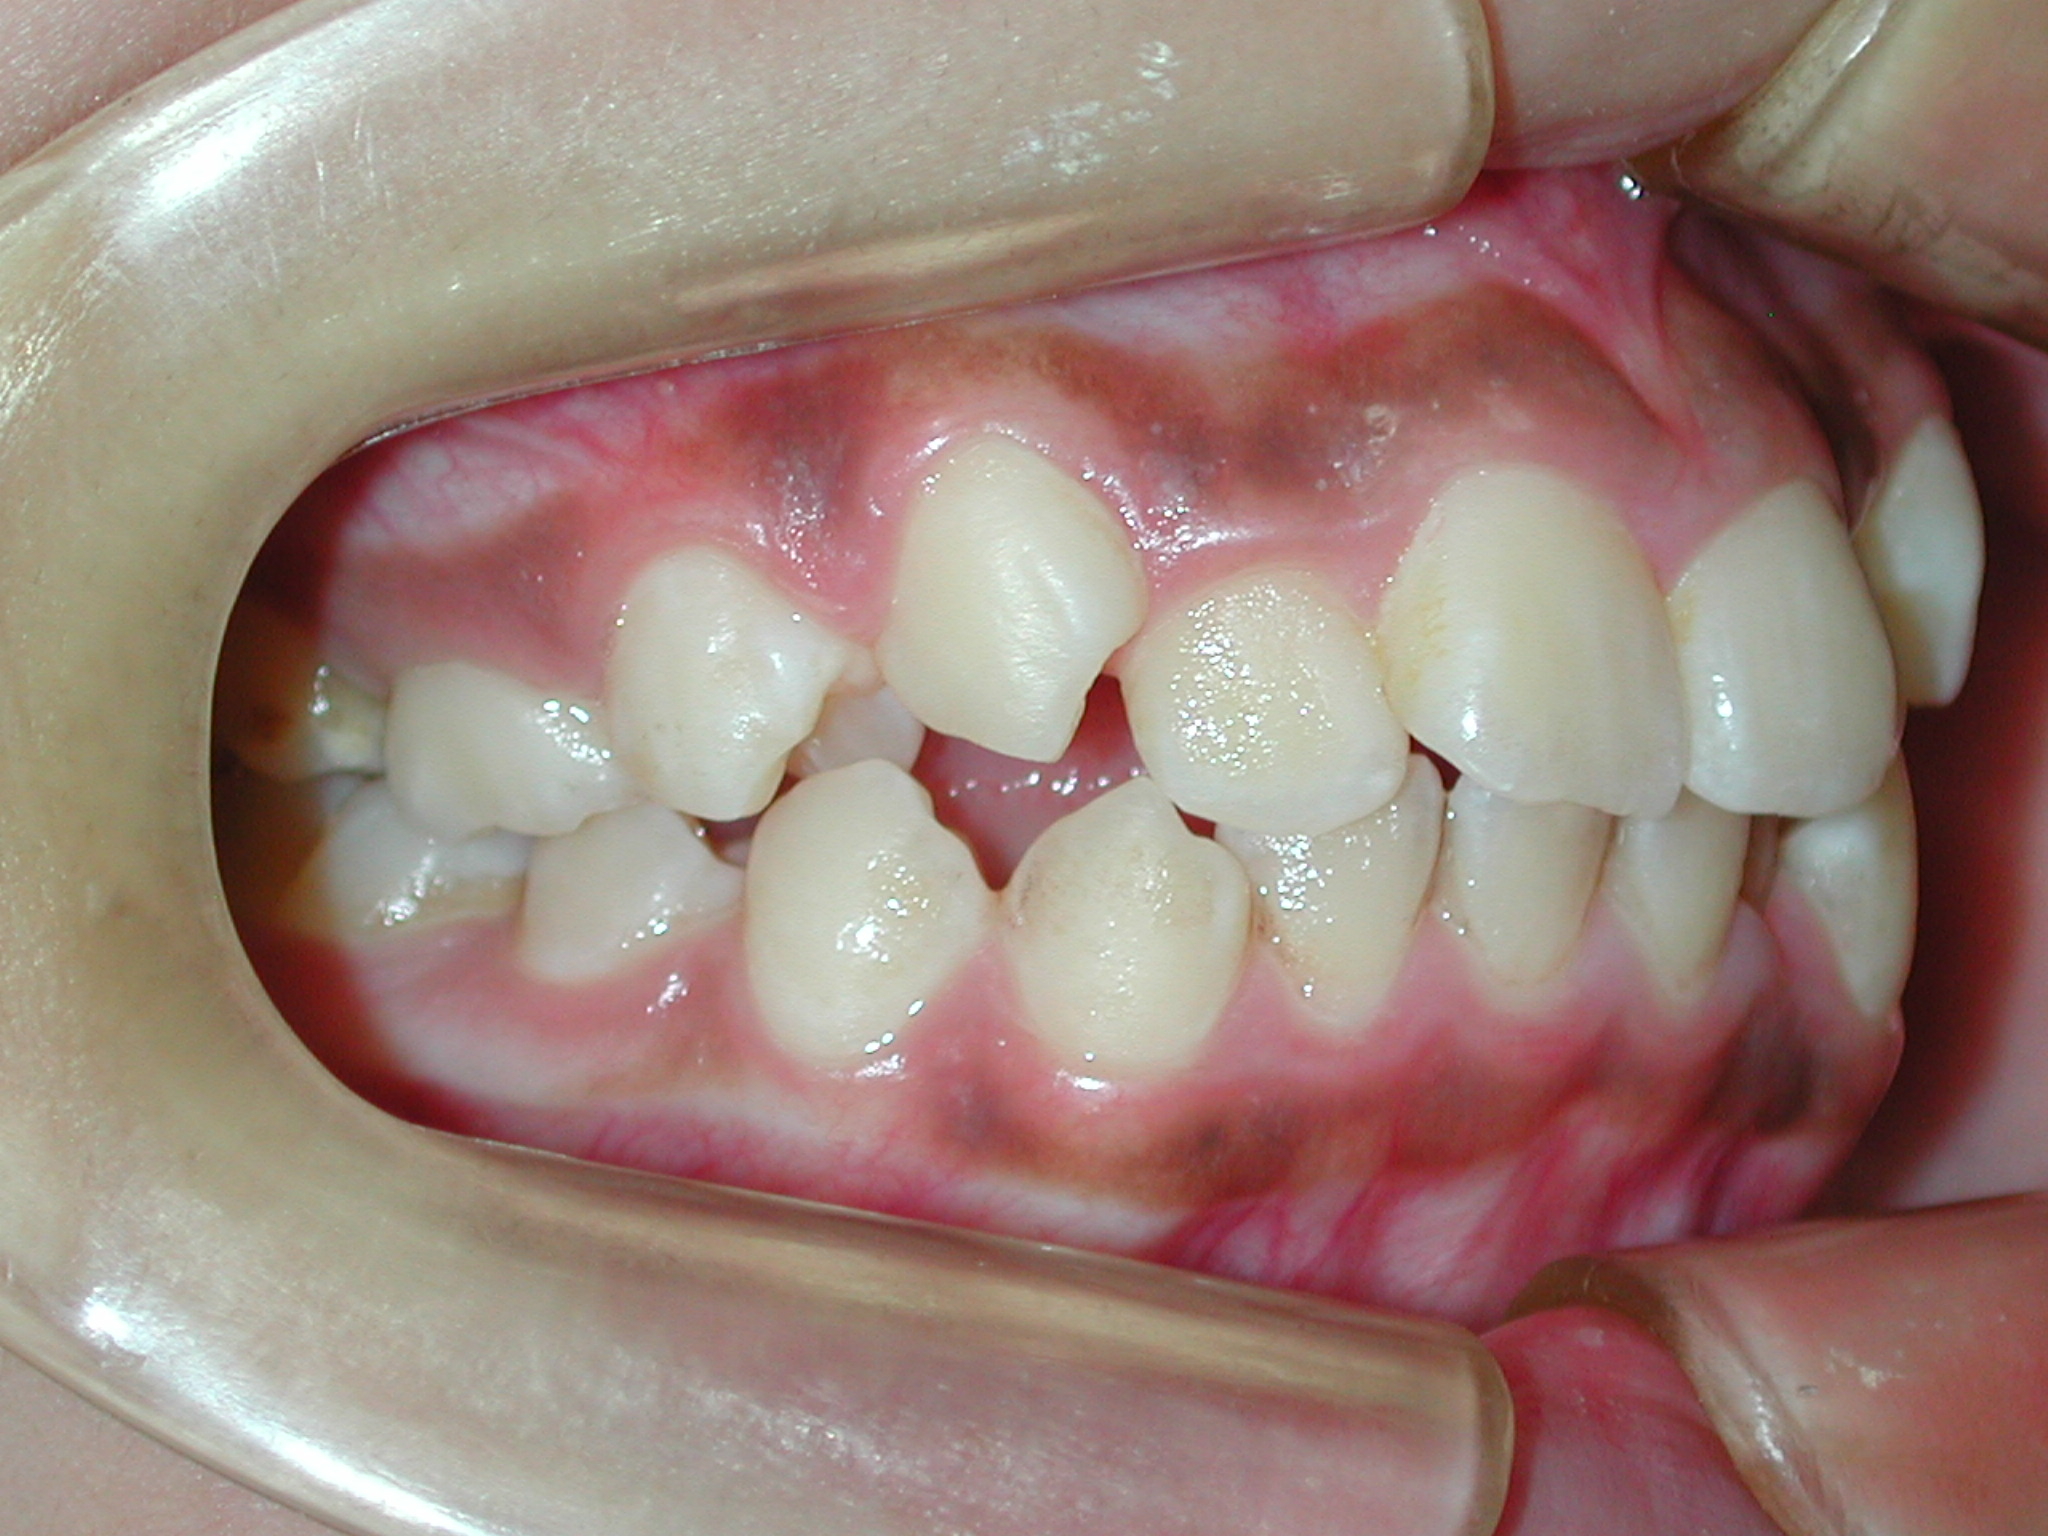

【主訴】10代女性: ご紹介で来院。八重歯とガタガタを抜歯しないで出来るだけ綺麗にしたい。他の歯科に矯正相談に行ったが小臼歯抜歯しないと治せない、抜歯しないと口元がだいぶ出てしまうと言われた。

【治療方法】新素材ゴムメタルを使用したGEAW(ギア)システム用い、小臼歯抜歯なしで治療を行いました。

【矯正治療前】